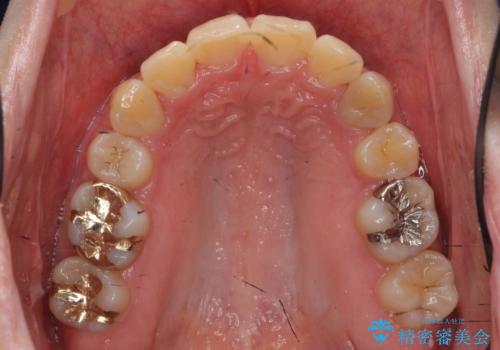

20代女性 前から5番目の歯を抜歯

- 前歯のがたつき、前突を主訴に来院。

通常前から4番目の歯を抜歯するのですが、左上5番の形が矮小であったため、そちらを抜歯しました。(患者様の希望にそっています。)

前から5番目の歯を抜くと、長くて1年ほど矯正期間が延長しますが、形に異常がない左上4番を抜かずに保存しています。